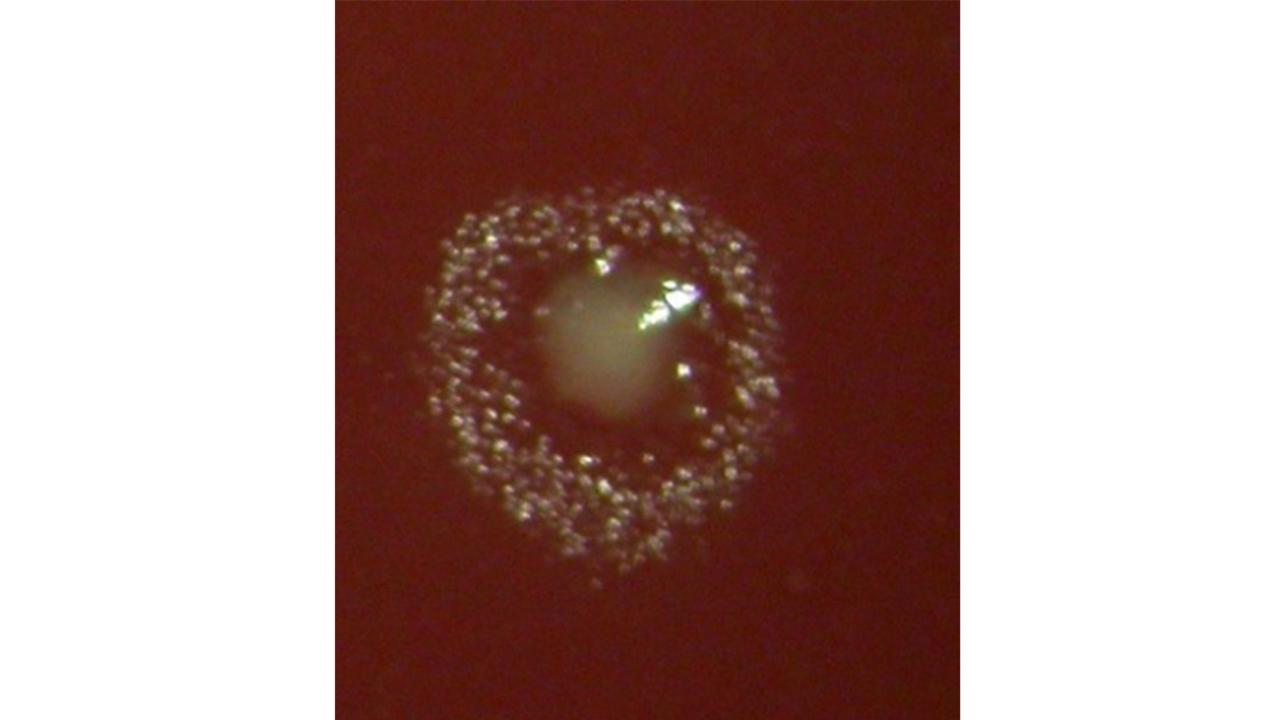

“As model organisms, we use, among others, Aggregatibacter actinomycetemcomitans, a bacterium that is often found in aggressive forms of periodontitis in younger people. We are also investigating Filifactor alocis, a relatively newly discovered possible pathogen in the oral cavity.”

“In a study among young people in Västerbotten, we found signs that saliva samples may be sufficient to analyse bacteria linked to periodontitis – a finding that was presented in Mark Lindholm’s doctoral thesis. In collaboration with researchers at Karolinska Institutet, we have also identified a previously unknown toxin and possible virulence factor in the bacterium Filifactor alocis. In a broader research collaboration, which also includes colleagues from the Department of Molecular Biology, we have shown that Aggregatibacter actinomycetemcomitans – a bacterium linked to aggressive forms of periodontitis – can be killed by its closest relative Aggregatibacter aphrophilus via a so-called type VI secretion system. Since A. aphrophilus, that is also found in the mouth, is not associated with the disease, the question arises: could it contribute to better oral health?”